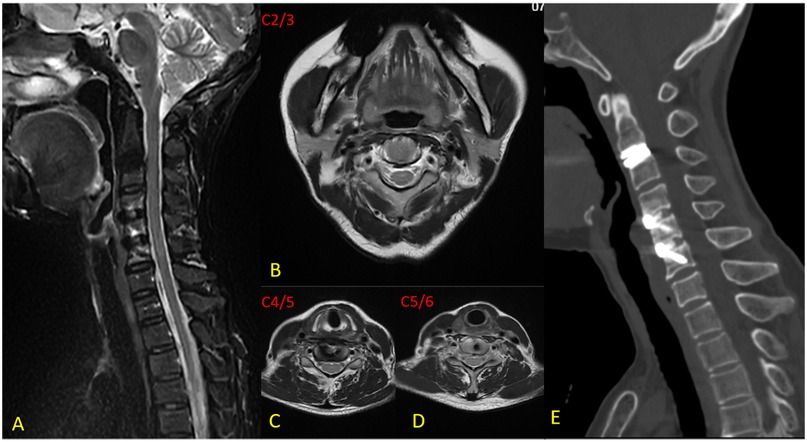

Background Cervical disc herniation at the C2-3 level, resulting in cervical spondylotic myelopathy (CSM), is an uncommon clinical entity. The diagnostic and therapeutic complexity escalates when this pathology coexists with non-contiguous multilevel cervical disc degenerative disease (CDDD). Due to the segmental variability in pathological features, the clinical manifestations of such cases are highly heterogeneous, thereby necessitating a highly individualized treatment strategy. Hybrid surgery (HS), which integrates cervical disc arthroplasty (CDA) and anterior cervical discectomy and fusion (ACDF), offers a tailored approach for the management of multilevel degenerative cervical pathology. The unique anatomical features and surgical technical challenges at the C2-3 level impose significant constraints on treatment options. This article presents a case of non-contiguous three-level hybrid surgery involving CDA at C2-3 and ACDF at C4-5 and C5-6, and discusses the feasibility of this technique for upper cervical disc pathology. Case Presentation A 62-year-old female was admitted with a 6-month history of neck and right upper limb pain, numbness, and gait instability, which had been unresponsive to conservative management. DR revealed loss of the normal cervical lordosis. CT showed no significant osteophyte formation or bony canal stenosis. MRI demonstrated a large disc extrusion at C2-3 causing spinal cord compression, and disc herniations at C4-5 and C5-6 with nerve root impingement. Based on clinical and imaging findings, a diagnosis of multilevel cervical spondylopathy (C2-3, C4-5, and C5-6 disc herniation) was established. The patient underwent anterior cervical discectomy followed by artificial disc arthroplasty (CDA) at C2-3, and anterior cervical discectomy and fusion (ACDF) at C4-5 and C5-6, successfully completing a non-contiguous three-level hybrid surgical procedure. Results Postoperative symptoms were significantly alleviated. At the 12-month follow-up, pain and gait disturbance had largely returned to normal. MRI confirmed adequate decompression of neural compression, DR demonstrated satisfactory range of motion (ROM) at C2-3, and CT revealed satisfactory bone healing at the fused segments. Conclusion CDA serves as an effective alternative for C2-3 disc pathology, achieving neural decompression while preserving segmental mobility. The HS provides a valuable surgical option for the precise treatment of non-contiguous multilevel degenerative disease.